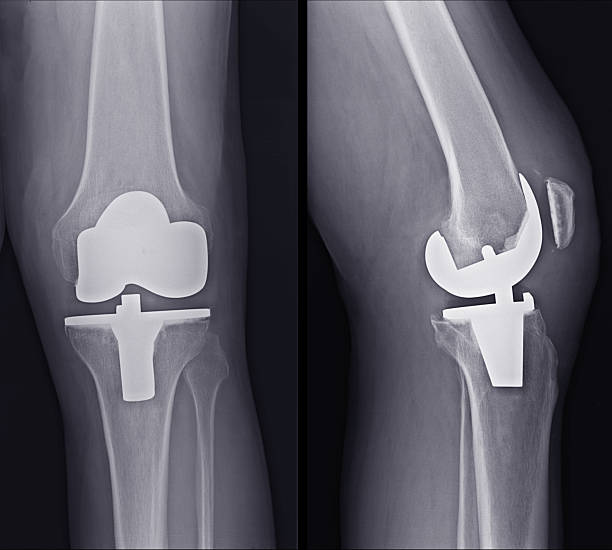

During a total knee replacement surgery, the damaged bone and cartilage are removed from the knee joint and replaced with artificial components. These components typically include a metal femoral component, a metal and plastic tibial component, and a plastic patellar component. The artificial parts are designed to mimic the natural movement of the knee, allowing for improved function and reduced pain. The surgery involves making an incision over the knee, removing the damaged tissue, and securing the new components to the bone using specialized cement or other fixation methods.

Partial and total knee replacements are surgical procedures designed to alleviate pain and restore function in patients with severe knee arthritis, but they differ significantly in their approach and scope. This procedure is less invasive, preserving more of the patient's natural knee structures, including the ligaments. In contrast, total knee replacement involves replacing all three compartments of the knee: the medial, lateral, and patellofemoral (front) compartments. This procedure is recommended for patients with widespread arthritis affecting the entire knee joint. During the surgery, the damaged bone and cartilage are removed and replaced with metal and plastic components designed to mimic the natural movement of the knee.